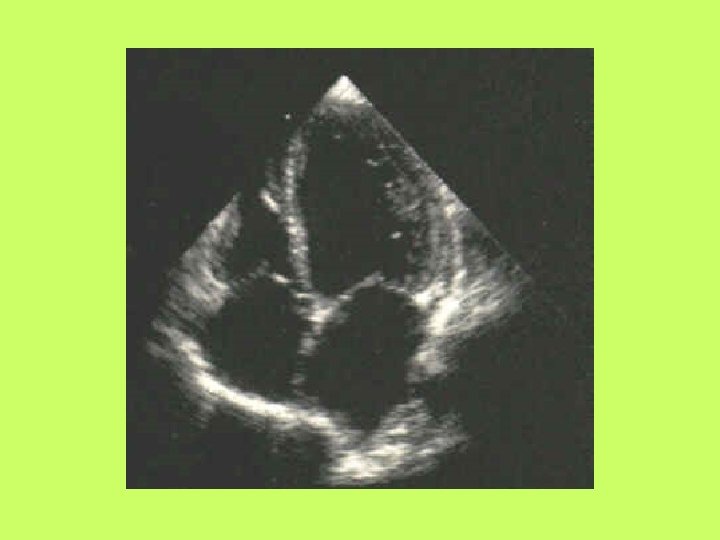

Noninvasive cardiac diagnostic studies 1 - EKG 2 -Chest X ray 3 -Exercise tolerance

Noninvasive cardiac diagnostic studies 1 - EKG 2 -Chest X ray 3 -Exercise tolerance test(ETT) 4 -Echocardiography transthoracic-trans esophagial 5 -Stress echocardiography 5 -Radionuclid imaging 6 -Cardiac catheterization